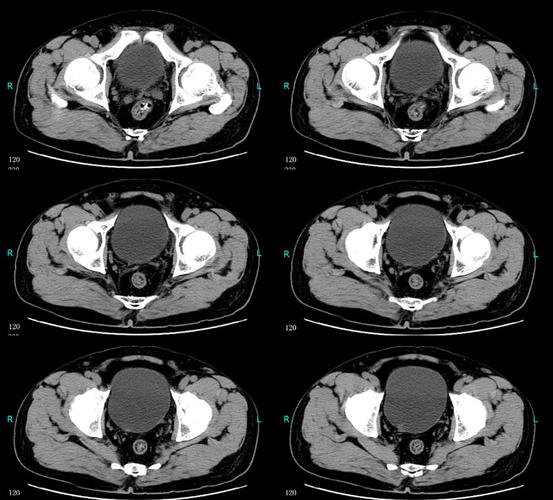

膀胱癌(低级别非浸润性尿路上皮癌)

患者ct结果—箭头处为膀胱肿瘤